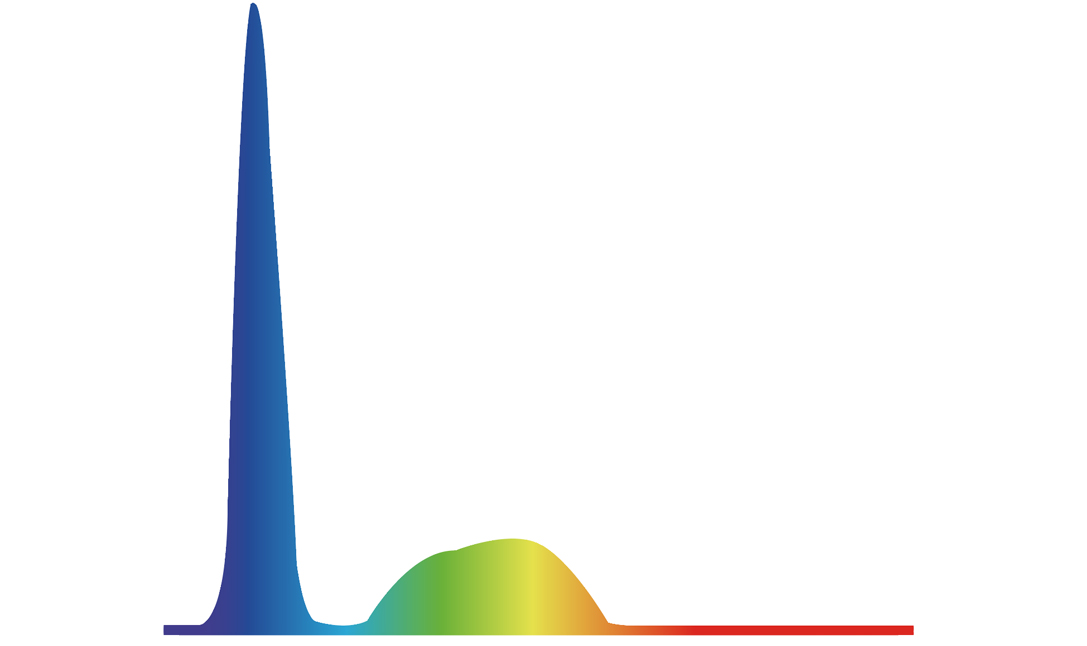

百老汇电子游戏官网新开发的内镜染色技术,主要是基于多波长LED 光源的开发,VLS-55Q 四波长LED 光源是由四个不同颜色的LED光按照相应照明模式所规定的特定发光比例进行合束后形成,合束后形成的照明光的光谱由红光、绿光、蓝光及蓝紫光这四个不同的波段范围构成。具有更高光谱自由度,通过光谱比例的控制,实现了聚谱成像技术,英文全称为“Spectral Focused Imaging, SFI”,缩写为“SFI”和光电复合染色成像技术,英文全称为“Versatile Intelligent Staining Technology, VIST”,缩写为“VIST”。